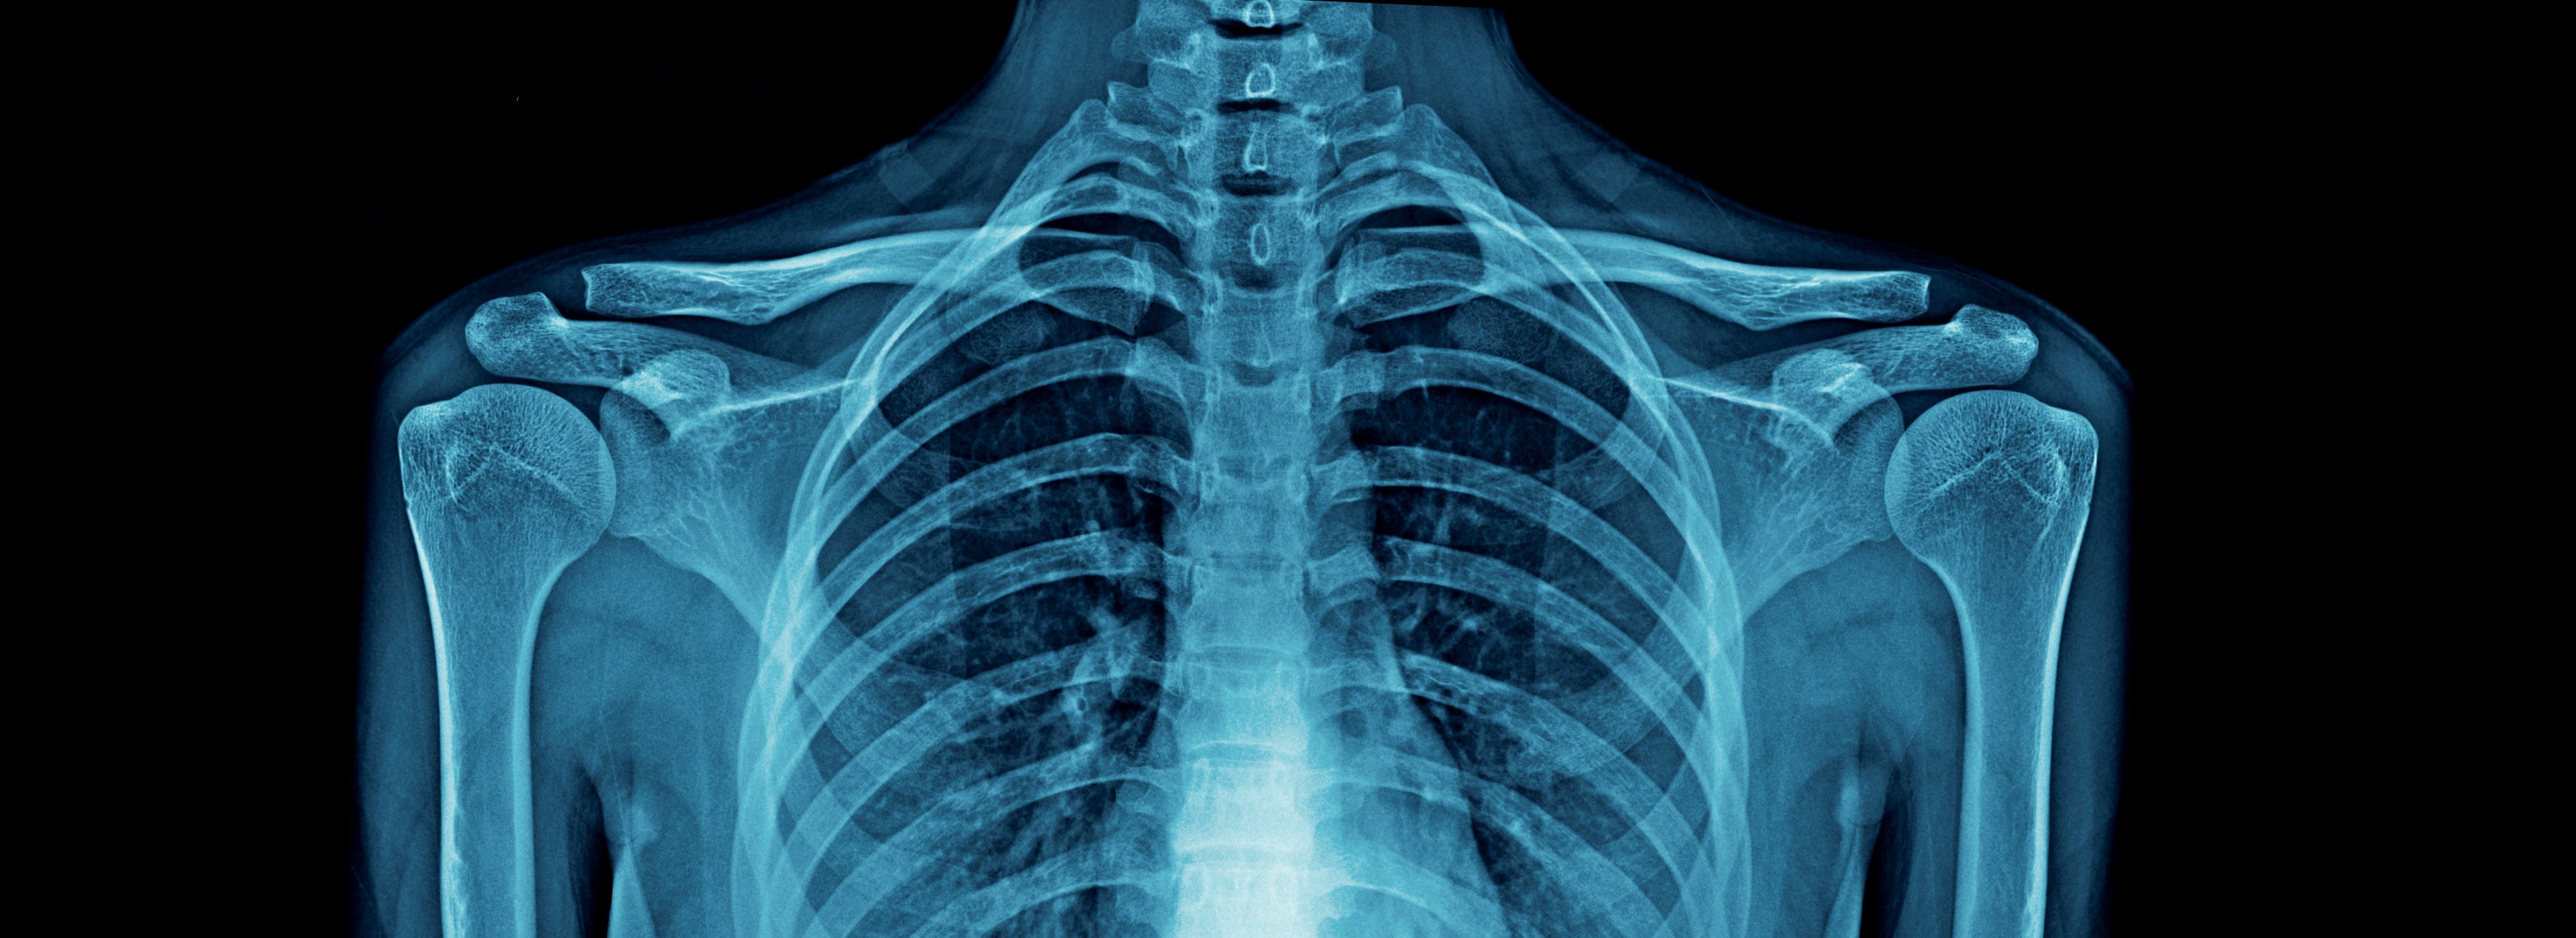

Digital X-rays allow our chiropractors to visualize the internal structures of your spine and surrounding tissues with incredible clarity. This cutting-edge technology enables us to:

- Identify Underlying Conditions: Pinpoint the root cause of your pain or discomfort, such as misalignments, degenerative disc disease, or fractures.

- Enhance Safety and Accuracy: Provide a detailed view of your spine to ensure safe and effective chiropractic adjustments.

Unlike traditional X-rays, digital X-rays use lower radiation levels and provide immediate results, allowing us to discuss your condition and treatment options during the same visit.